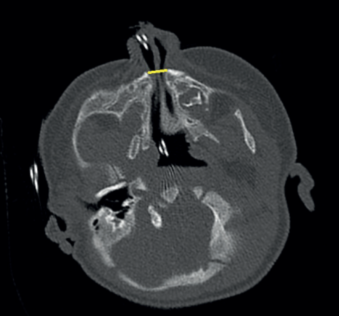

A los 50 días de vida consulta en urgencias por dificultad respiratoria y rechazo de las tomas secundarios a infección respiratoria superior agravada por la anatomía de la paciente. A la exploración física se evidencia paladar ojival en V, hipotelorismo, raíz nasal plana con anteversión de narinas (ya objetivados en controles de seguimientos previos, más evidentes con el crecimiento de la paciente). Se decide ampliar estudio con TAC de cabeza y senos paranasales donde se objetiva estenosis de orificios piriformes (Figura 1) (derecho de 4 mm, izquierdo de 1,2 mm) por medialización del proceso nasal del hueso maxilar que asocia desviación del tabique nasal al lado izquierdo junto a paladar duro hipoplásico con morfología triangular y megaincisivo central único en maxilar superior (Figura 2). Se realiza resonancia magnética (RM) cerebral donde no se visualizan otras alteraciones en cerebro, cerebelo o tronco con hipófisis presente en silla turca de aspecto normal. Se realiza nasofibrolaringoscopía objetivando estrechez de narinas y fosas nasales que dificulta el paso del fibroscopio hasta laringe. Radiografía de tórax y serie ósea, ecografía abdominal, ecocardiografía sin alteraciones. Estudio analítico (incluido perfil tiroideo) normal. Es dada de alta con alimentación por sonda nasogástrica bajo seguimiento estrecho en consultas de dismorfología, donde se completa estudio genético con cariotipo 46 XX y CGH Array en el que no se detectan variaciones de cambio de número de copia de naturaleza no polimórfica.

Figura 2: TAC craneal. Megaincisivo central maxilar medio único.